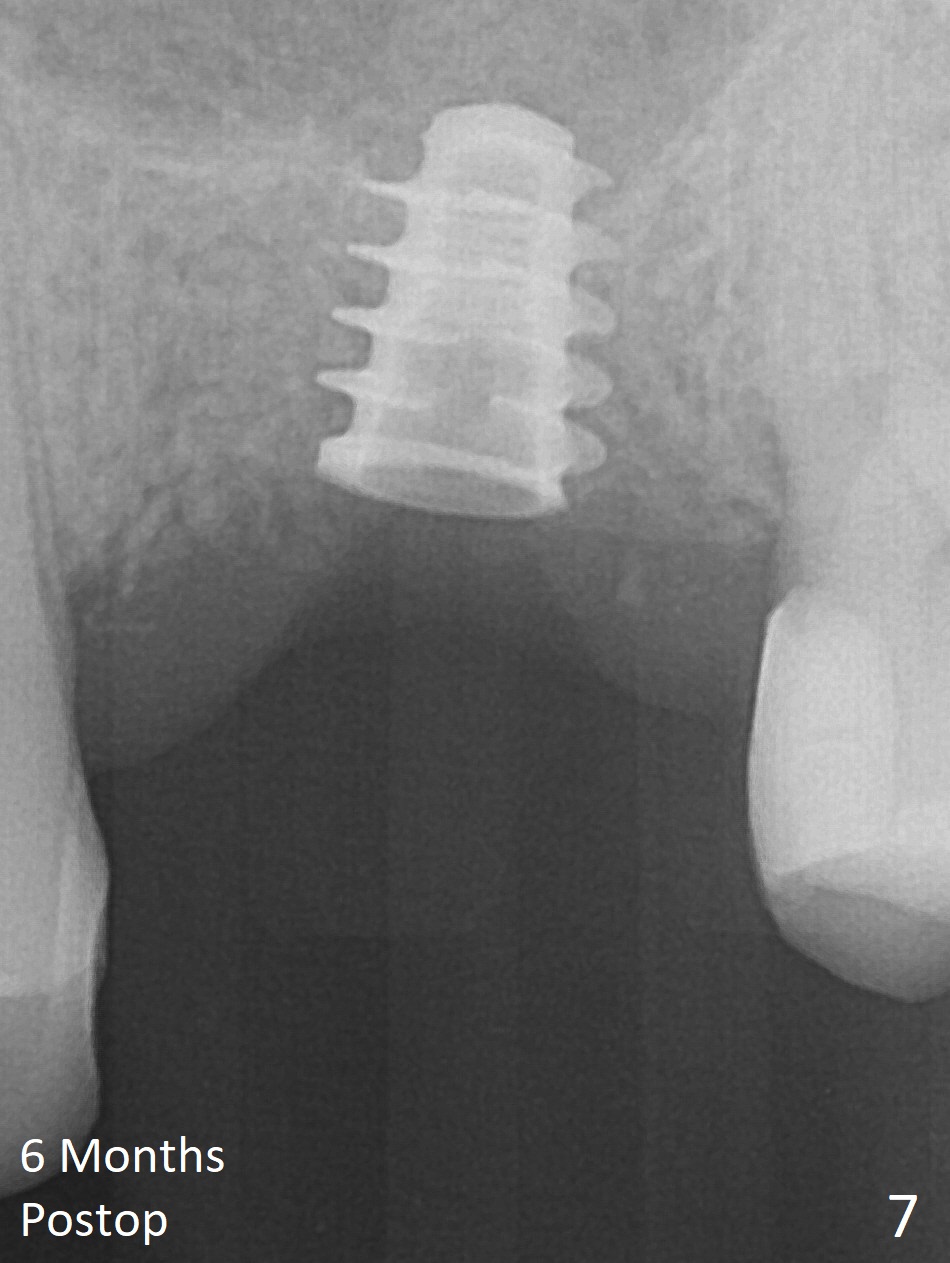

The implant is mobile 4 months postop (Fig.6). A 6x2 mm healing abutment is placed next. Although the implant remains mobile 6 months postop, the bone seems to have become denser around the implant (Fig.7-9). A healing screw is placed. When the bone height is limited (<7 mm), place a larger implant (>5.5 mm). The implant seems to have osteointegrated 8 months postop (Fig.10). Impression is taken following placing a 6.5x4(3) mm abutment. The patient reports pain after cementation, which is less when the abutment screw is loose (9.5 months postop, 2 weeks post cementation). CBCT taken after placement of a healing screw apparently shows loose bone mesial and distal to the implant (Fig.11 *). The implant trajectory is less favorable. It seems necessary to change to a large implant with more sold threads (Fig.12).